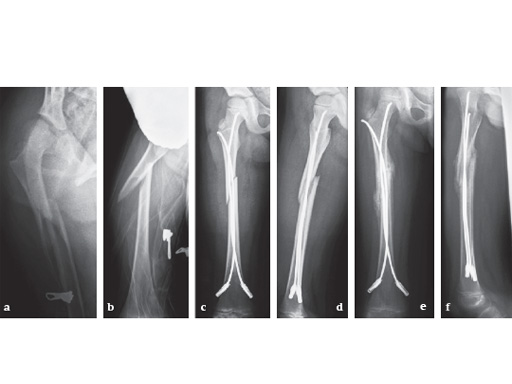

12-year-old boy; snow-board injury long spiral proximal femoral fracture (32D/5.1) primary indication for operation with ESIN and End Cap.

cd

Postoperative x-rays show a correct alignment and length. Fixation with 3.5 mm TEN and End Caps was performed.

e

This detail view shows the correct positioning of the End Caps.

fg

4 1/2 weeks postoperative a good callus and correct alignment was visible, full weight bearing was allowed.